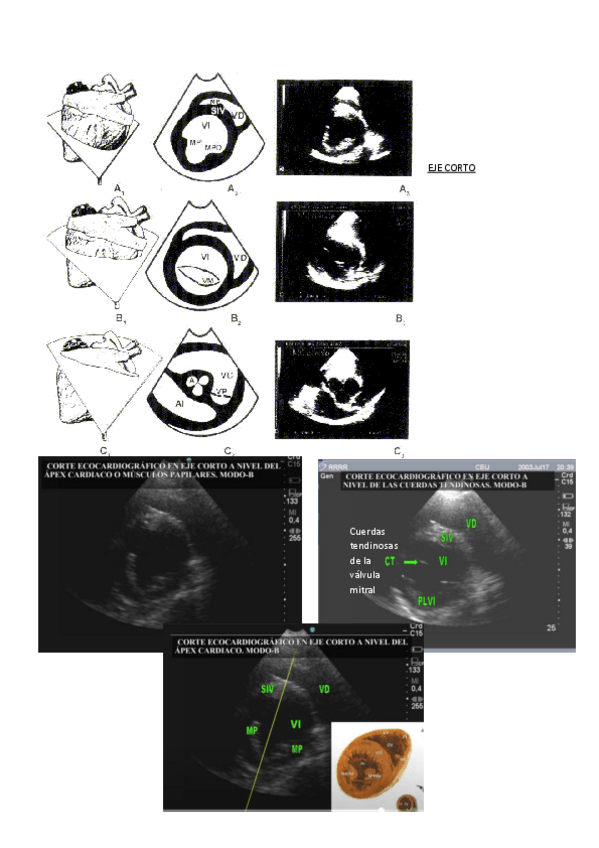

He publicado nuevos apuntes de 3º Técnicas de diagnóstico clínico II (Diagnóstico por imagen): ECOCARDIOGRAFIA.pdf